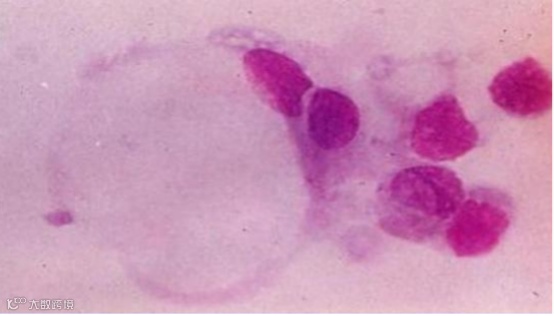

胃印戒细胞癌,之所以叫这个名字,就是因为它的癌细胞形态呈“戒指”样。

图:印戒细胞癌

胃印戒细胞癌起源于胃黏膜上皮,是一种含有大量黏液的特殊胃癌类型,由于细胞中充满了黏液,把细胞核挤向了细胞的一侧,使其外形酷似一枚戒指。